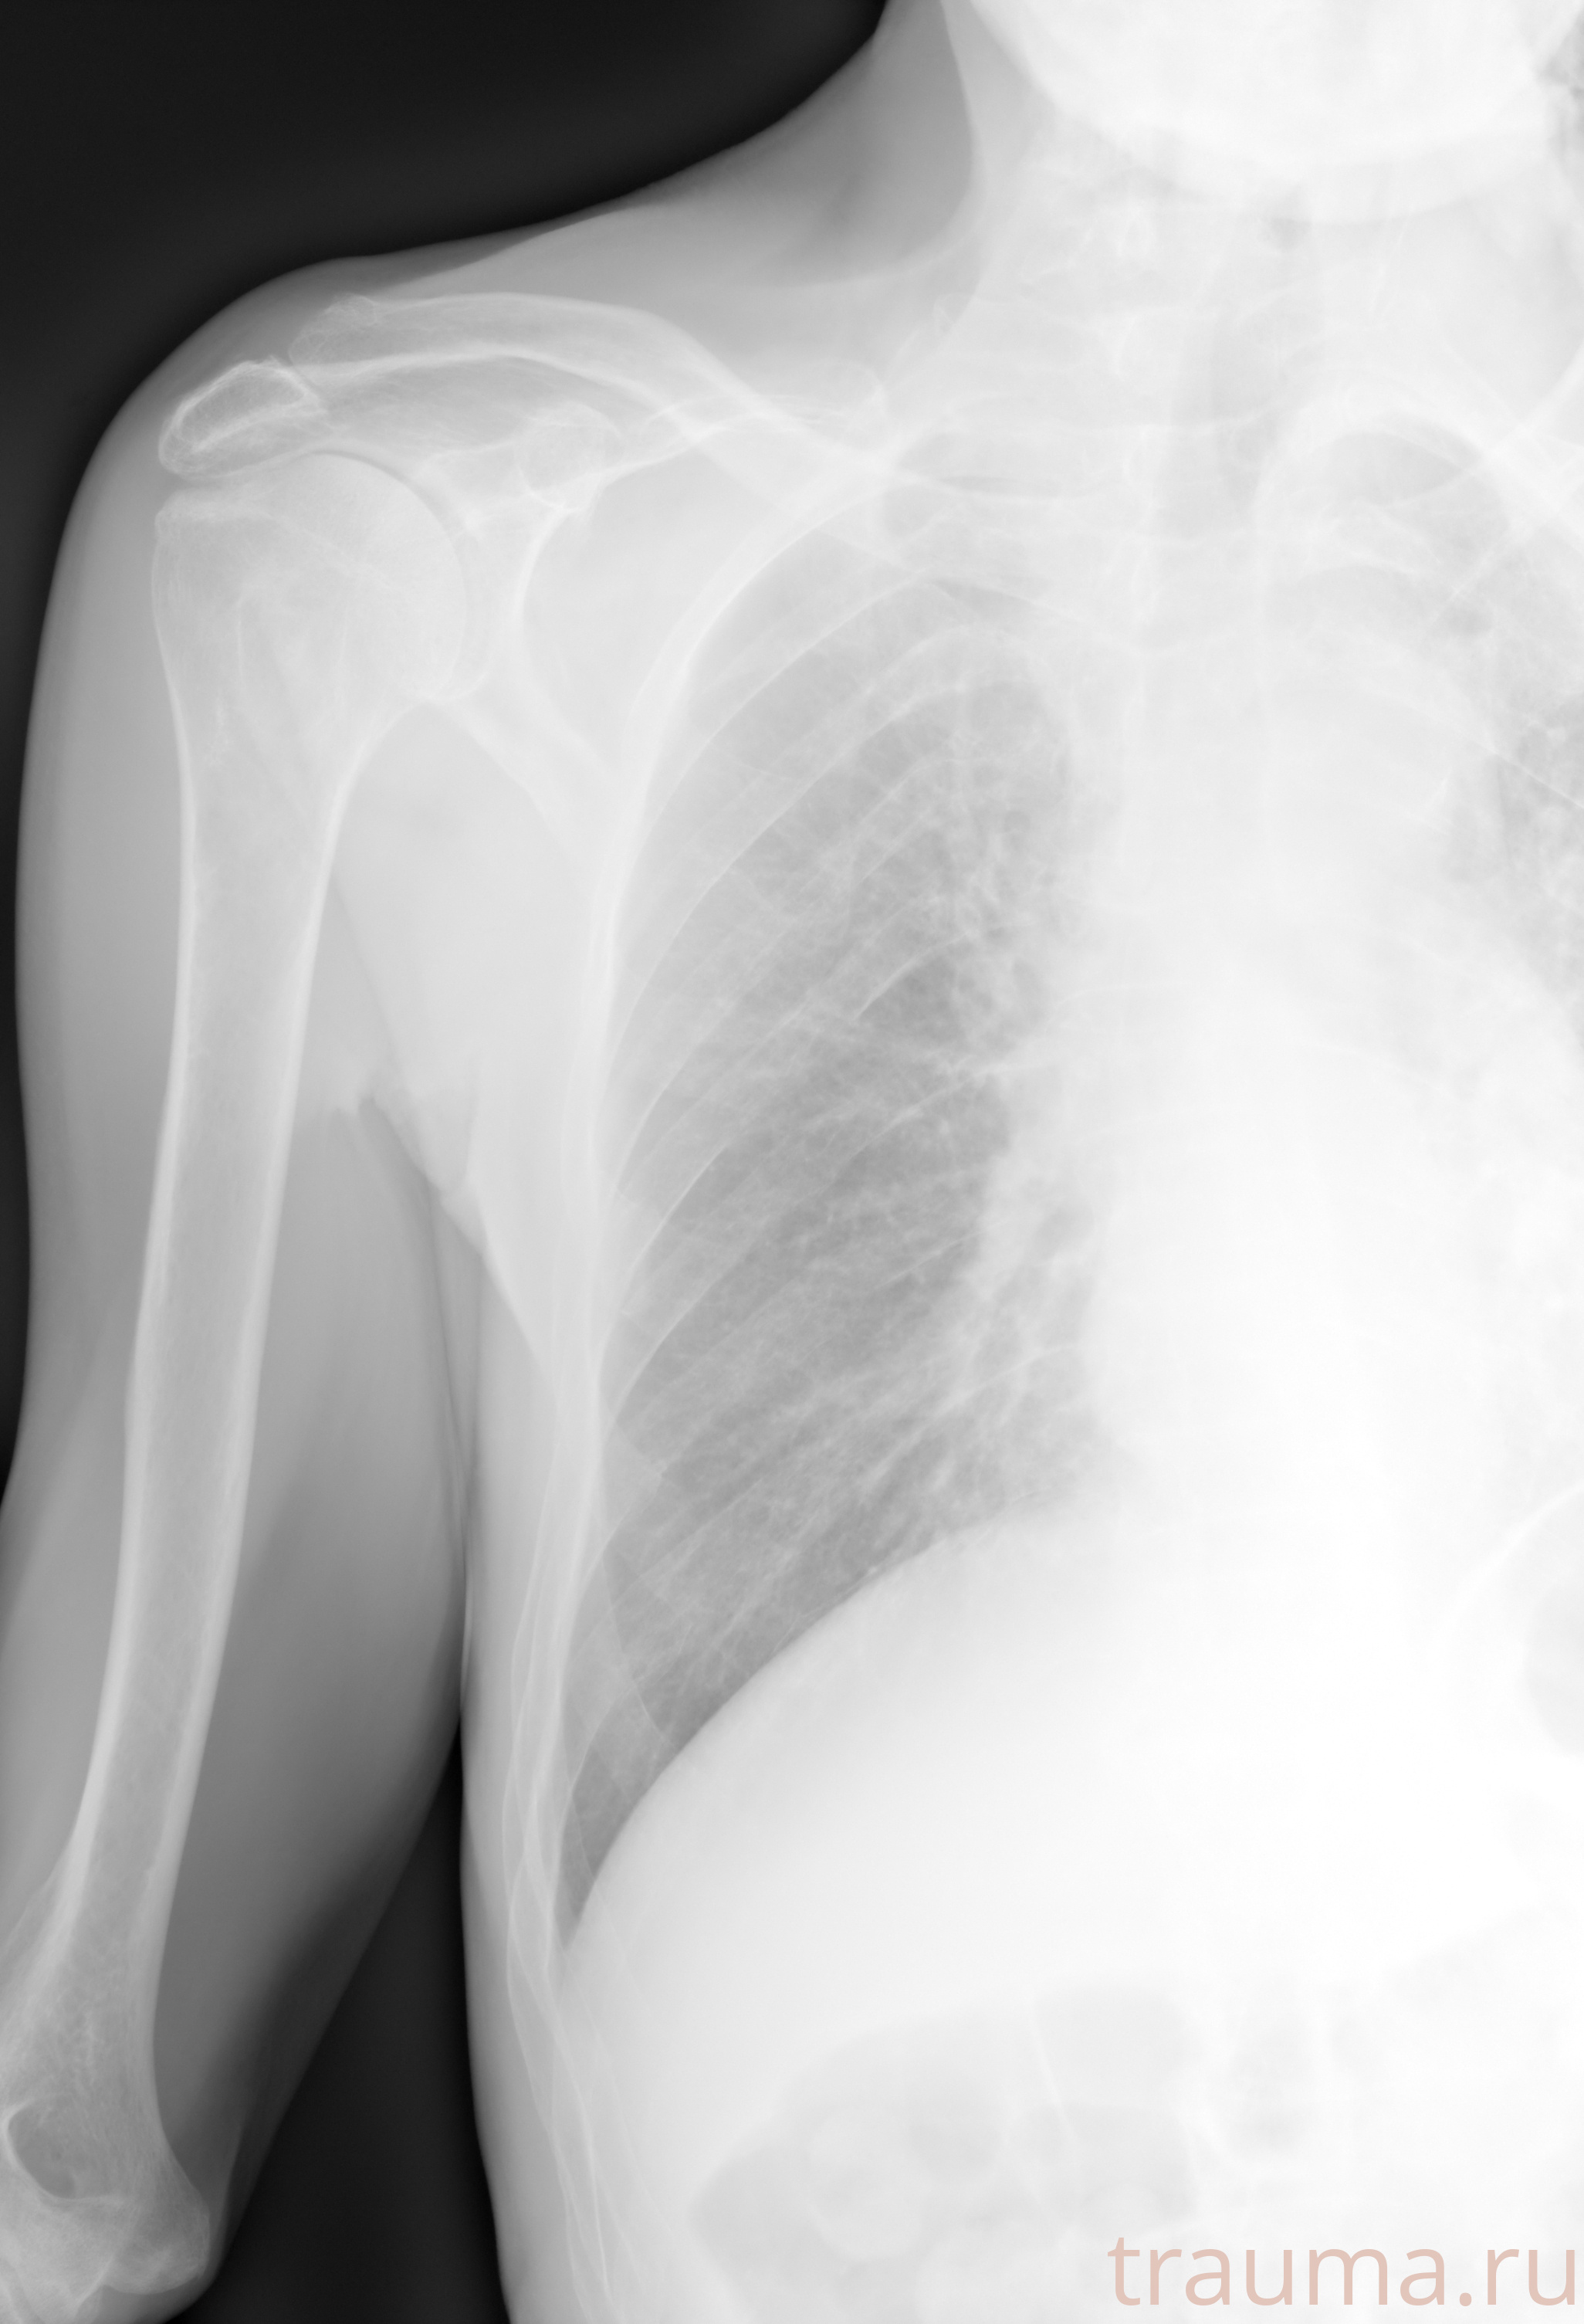

Рентгенограммы

Рентген на дому: по вашему адресу приезжает врач-рентгенолог, травматолог-ортопед с мобильным рентгеновским аппаратом, проводит диагностику травмы или заболевания, делает необходимые рентгенограммы, дает рекомендации по дальнейшему лечению. Получить качественные снимки в домашних условиях возможно благодаря уникальной методике, разработанной МосРентген Центром для института  Склифосовского